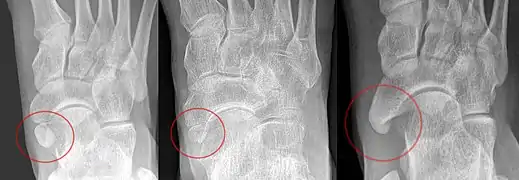

An accessory bone or supernumerary bone is a bone that is not normally present in the body, but can be found as a variant in a significant number of people. It poses a risk of being misdiagnosed as bone fractures on radiography.[2]

Wrist and hand

| Accessory bone | Prevalence on the right (R) and left (L)[5] |

|---|---|

| Os ulnostyloideum | 1.5% R, 2.4% L |

| Os centrale | 1.3% R, 2.1% L |

| Os trapezium secundarium | 0.5% R, 2.1% L |

| Os styloideum | 1.2% R, 1.2% L |

| Os radiale externum | 1% R, 0.9% L |

| Os triangulare | 1% R, 0.9% L |

| Os paratrapezium | 0.3% R, 0.9% L |

| Os capitatum secundarium | 0.8% R, 0.3% L |

| Os Hypotriquetrum | 0.5% R |

| Os hypolunatum | 0.3% L |

| Os epilunatum | 0.3% R, 0.3% L |

| Os ulnare externum | 0.3% L |

| Os pisiforme secundarium | 0.3% R |

| Os epitrapezium | 0.3% L |

| Os vesalianum manus | 0.3% L |

Os ulnostyloideum

The os ulnostyloideum is an ulnar styloid process that is not fused to the rest of the ulna bone.[6] On X-rays, an os ulnostyloideum is sometimes mistaken for an avulsion fracture of the styloid process. However, the distinction between these is extremely difficult.[6][7] It is alleged that the os ulnostyloideum has a close relationship with or is synonymous with the os triquetrum secundarium.[8]

Os centrale

The os carpi centrale (also briefly os centrale) is, where present, located on the dorsal side of the wrist between the scaphoid, the trapezoid and capitate, radially to the deep fossa of the capitate. The bone is present in almost every human embryo of 17–49 mm length, but then usually fuses with the ulnar side of the scaphoid. Sometimes it fuses with the capitate or the trapezoid. The literature also refers to an os centrale at the palm of the carpus, but this existence is questioned.[6]